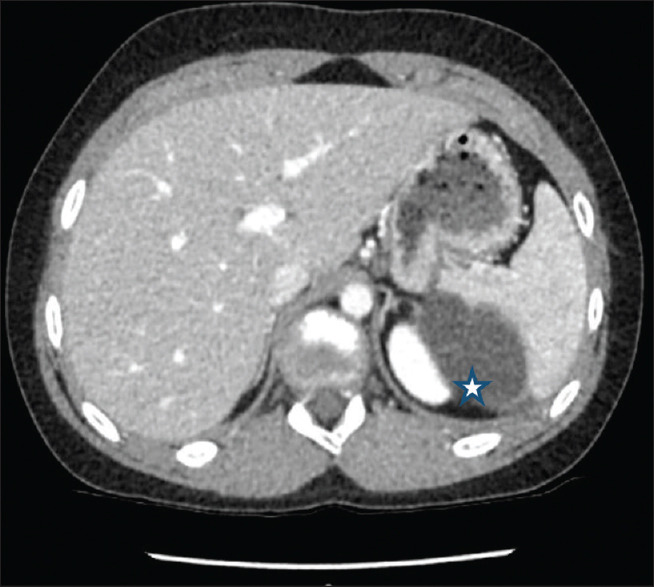

摘要:脾表皮样囊肿是一种罕见的儿童良性肿瘤,占脾脏所有囊性病变的 10%,是非寄生虫性脾囊肿中最常见的诊断方法。它可能是偶然发现的,也可能是在肿块或腹痛的影像检查后发现的。由于全脾切除术使患者面临脾切除术后感染的风险,腹腔镜脾部分切除术在过去二十年中越来越受欢迎,因为它保留了脾脏的免疫功能。由于出血风险较高,这项技术只能由训练有素的团队进行。作者报告了三例接受腹腔镜脾脏部分切除术的患者:一名无相关病史的 7 岁女孩,脾脏下极有一个 4.5 厘米大的表皮样囊肿;一名接受胰岛素治疗的 13 岁 1 型糖尿病男孩,脾脏上极有一个 7 厘米大的表皮样囊肿;一名无病史的 14 岁女孩,脾脏上极有一个 6 厘米大的表皮样囊肿。手术时间分别为2小时30分钟、3小时和4小时30分钟。术中失血量分别为 100 毫升、350 毫升和 300 毫升。每位患者的住院时间均为 6 天。围手术期未进行输血。平均随访时间为 21 个月(分别为 32 个月、21 个月和 10 个月),没有发生并发症或复发。

Abstract: Epidermoid splenic cyst is a rare benign tumour in children, accounting for 10% of all cystic lesions of the spleen and is the most common diagnosis of non-parasitic splenic cysts. Its discovery could be incidental or happen after an imaging workup for a mass or abdominal pain. Since total splenectomy exposes a patient to the occurrence of overwhelming post-splenectomy infection, laparoscopic partial splenectomy has been increasingly popular over the past two decades because it preserves the immune function of the spleen. This technique should only be performed by a well-trained team because of the high risk of bleeding. The authors report the cases of three patients who underwent laparoscopic partial splenectomy: a 7-year-old girl with no relevant history with a 4.5-cm epidermoid cyst involving the lower pole of the spleen, a 13-year-old boy, type 1 diabetic on insulin therapy, with a 7-cm epidermoid cyst of the upper pole of the spleen and a 14-year-old girl, with no previous history, with a 6-cm upper pole epidermoid splenic cyst. Operating times were 2 h 30 min, 3 h and 4 h 30 min, respectively. The intraoperative blood loss was 100 mL, 350 mL and 300 mL, respectively. The length of hospital stay was 6 days for each patient. No blood transfusion was performed perioperatively. With a mean follow-up duration of 21 months (32 months, 21 months and 10 months, respectively), no complication or recurrence occurred.